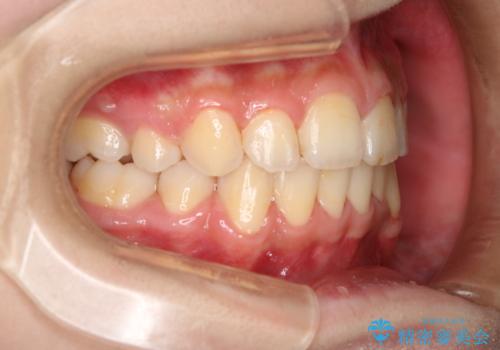

出っ歯と深い噛み合わせ:抜歯矯正で口元スッキリ!

- 出っ歯が気になるとご相談にいらした方です。抜歯して歯を並べました。深かった噛み合わせも改善させることが出来ました。

噛み合わせが元々深い方は一般的に噛む力が強く、治療に時間がかかる傾向にあります。治療前の想定よりも短期間でスムーズに治療を終える事ができ、大変喜んでいただけました。リテーナーによる保定もしっかり行っていただいており、後戻りなく快適にすごして頂けているとのことです。